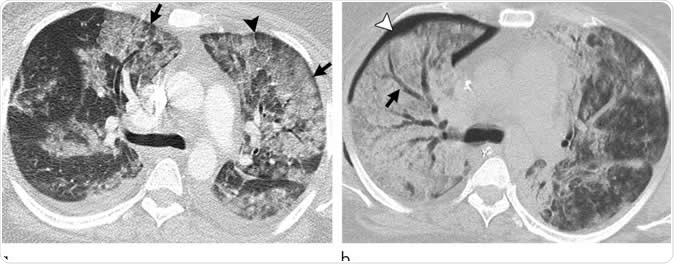

Images show electronic cigarette or vaping product use-associated lung injury with diffuse alveolar damage pattern in a 35-year-old woman who vaped tetrahydrocannabinol. Work-up for infection and rheumatologic disease was negative. (a) Axial CT scan shows ground-glass opacity, left greater than right, with areas of consolidation. Subpleural and perilobular sparing is present (arrows). Septal thickening is present (arrowhead). (b) CT scan 2 weeks later shows extensive right lung consolidation with areas of bronchial dilation (arrow) and internal development of right pneumothorax (arrowhead). Ground-glass opacity in left lung has improved with residual centrilobular nodularity. Patient died 5 days later.  CREDIT Radiological Society of North America

Images show electronic cigarette or vaping product use-associated lung injury with diffuse alveolar damage pattern in a 35-year-old woman who vaped tetrahydrocannabinol. Work-up for infection and rheumatologic disease was negative. (a) Axial CT scan shows ground-glass opacity, left greater than right, with areas of consolidation. Subpleural and perilobular sparing is present (arrows). Septal thickening is present (arrowhead). (b) CT scan 2 weeks later shows extensive right lung consolidation with areas of bronchial dilation (arrow) and internal development of right pneumothorax (arrowhead). Ground-glass opacity in left lung has improved with residual centrilobular nodularity. Patient died 5 days later. Image Credit: Radiological Society of North America